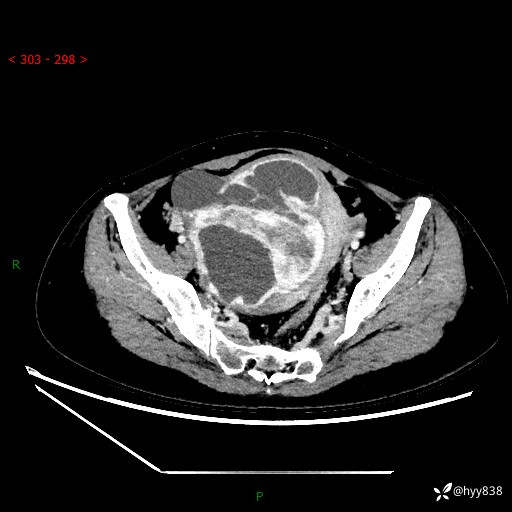

辅助检查:CT

盆腔CT平扫

增强(动脉期+静脉期)